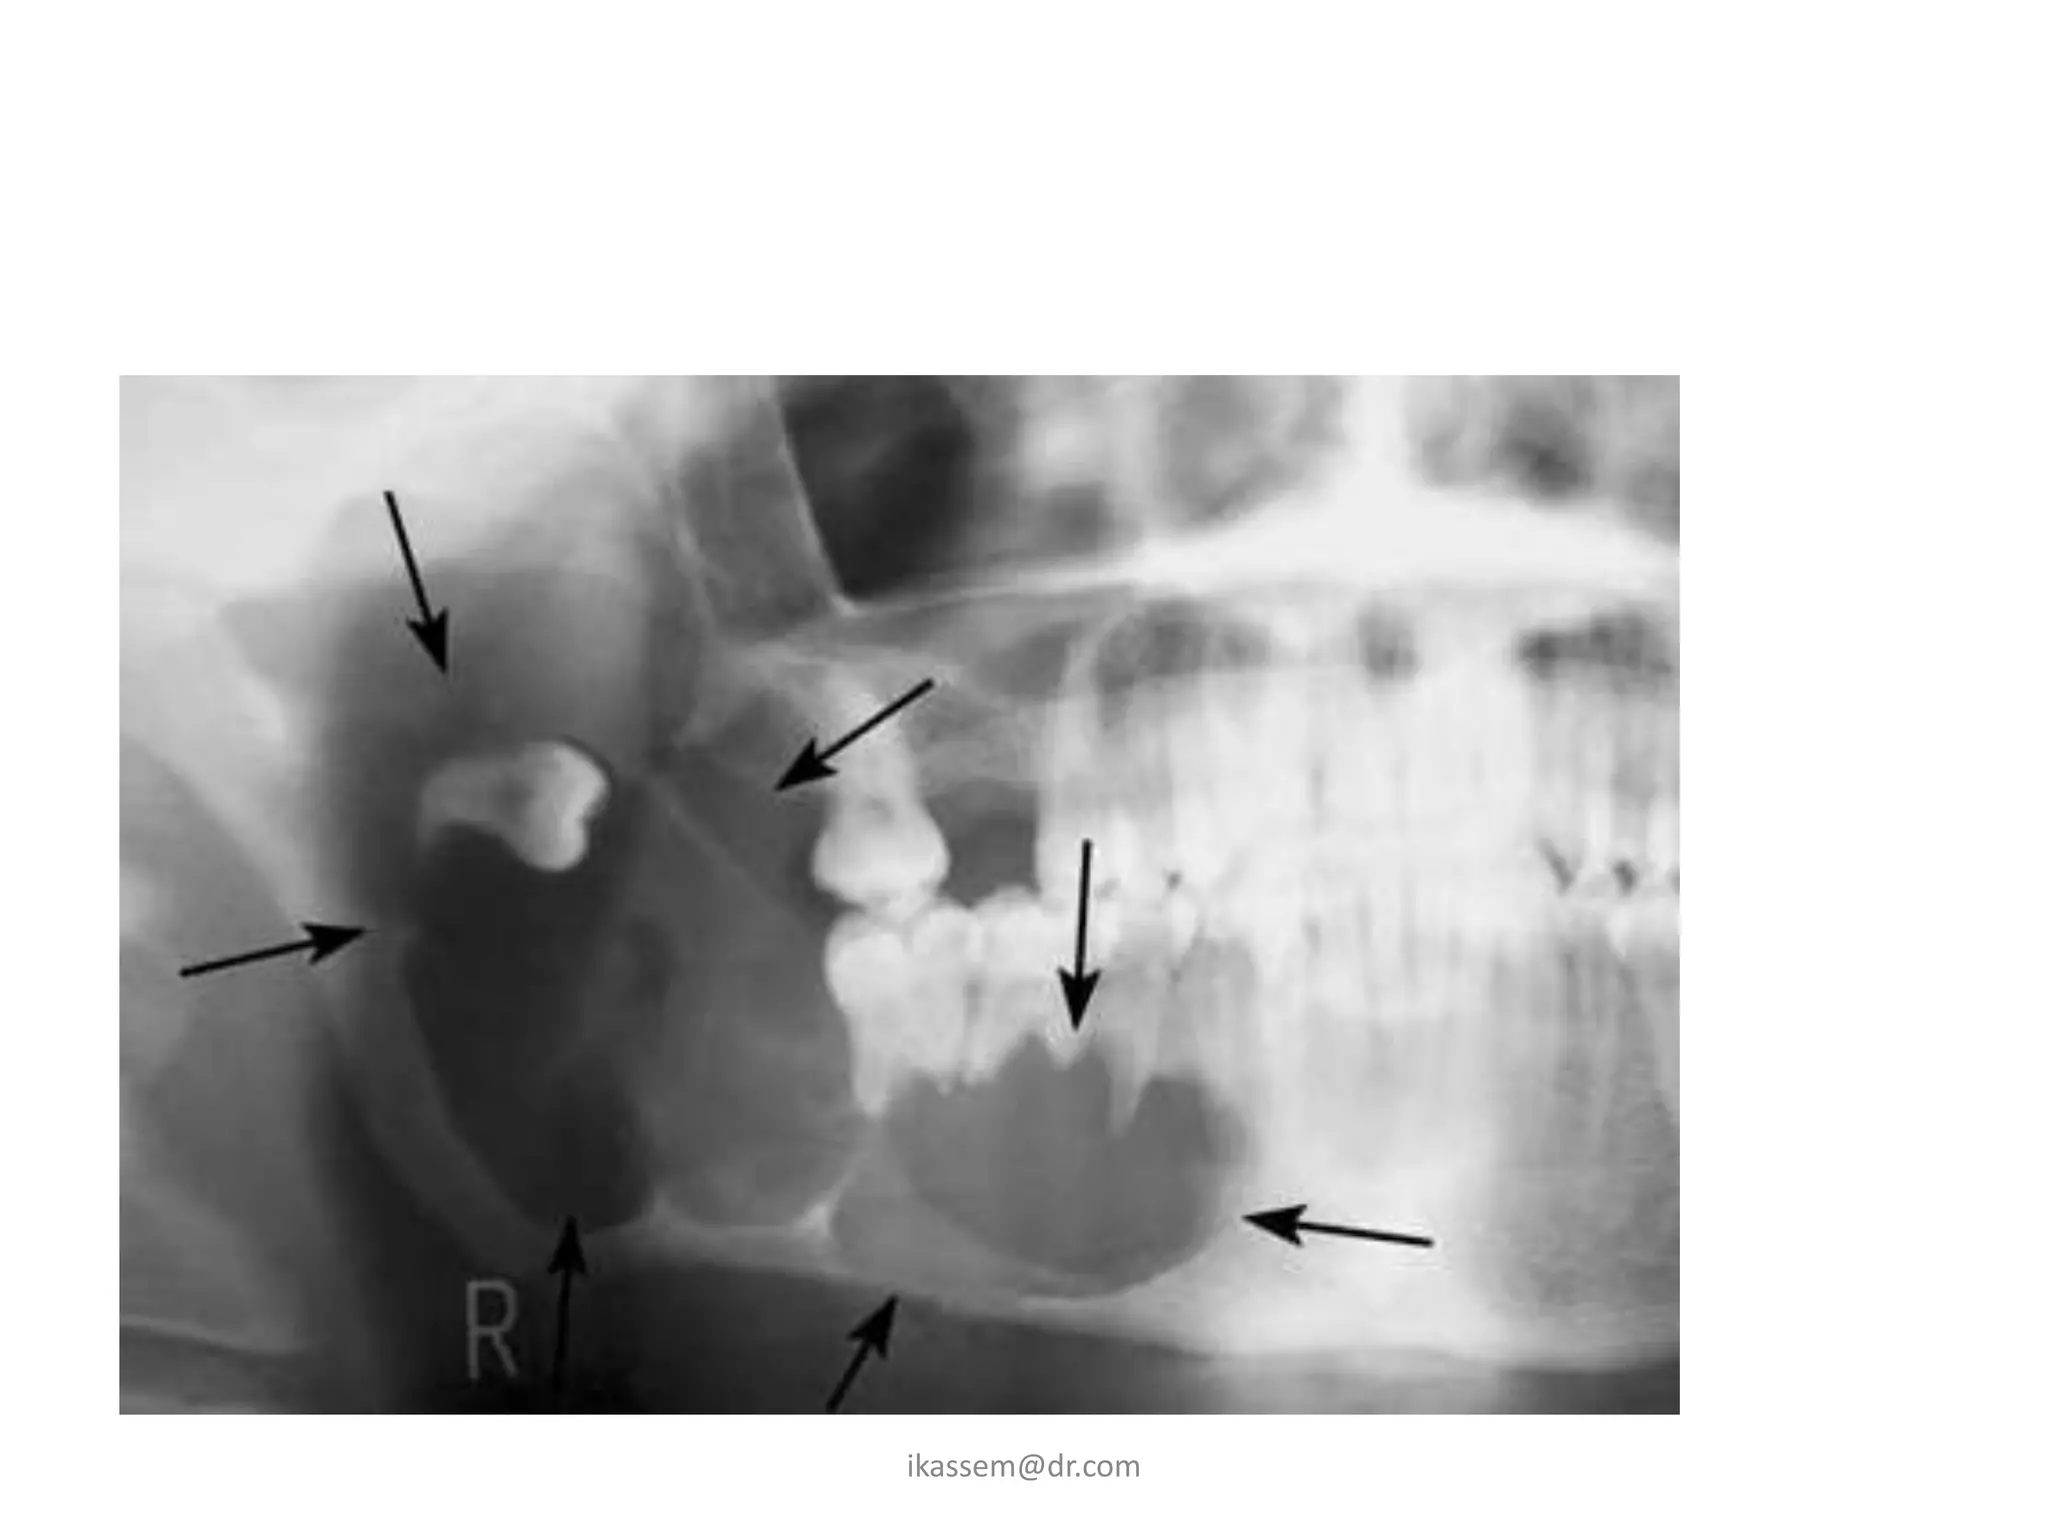

1-Classification of impacted

mandibular third molar:

A - Relation of the tooth to the ascending

ramus of the mandible and to the distal

surface of the 2nd molar: (Pell &Gregory)

– this show the anterioposterior relationship of the

tooth to the arch and the amount of resistance

offered by the bone of the ascending ramus that may

influence the tooth removal

Class1

• the space between the

anterior part of the

ascending ramus and

the distal surface of the

2nd molar is sufficient

to accommodate the

mesiodistal diameter of

the crown of the third

molar.

Class2

distal surface of the 2nd

molar is less than the

molar (part of the tooth

located within the

ramus)

Class3

• all the third molar is

ascending ramus of the

mandible.

B - Relative depth of the third molar in

bone:

- this show the superior inferior

relationship of the tooth in

relation to the occlusal plan. (Pell

& Gregory)

• Position A:

the highest portion of the tooth is on level

with or above the occlusal plane.

• Position B:

the highest portion is below the occlusal

plane but above the cervical margin of the 2nd

molar

• Position C:

the highest point of the tooth is below the

cervical margins of the 2nd molar (deep

impaction)